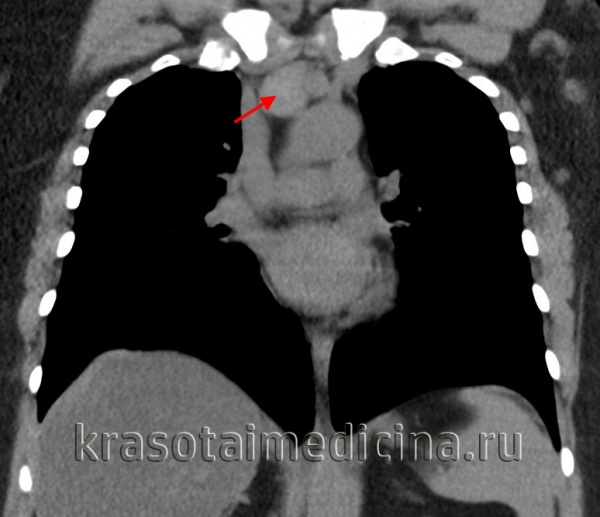

(б) У этой же пациентки при КТ с контрастным усилением визуализируется крупный мягкотканный конгломерат, включающий в себя преваскулярные, паратрахеальные лимфатические узлы и лимфатические узлы корней легких. Следует отметить наличие умеренного плеврального выпота справа, альвеолярной инфильтрации и узелков в правом легком, что соответствует вовлечению в опухолевый процесс легкого. (а) У этой же пациентки при ФДГ-ПЭТ/КТ определяется повышенный уровень поглощения ФДГ различными лимфатическими узлами средостения и корней легких. Следует отметить накопление ФДГ паренхимой легкого, что свидетельствует о вовлечении его в опухолевый процесс. Также обращает на себя внимание интенсивное поглощение ФДГ подмышечными лимфатическими узлами с обеих сторон.

(б) Молодой мужчина с лимфомой Ходжкина. При КТ с контрастным усилением в переднем средостении визуализируется объемное образование гетерогенной структуры с дольчатым контуром. В структуре образования выявляются отдельные зоны пониженной плотности, соответствующие зонам некроза. (а) Пациент с нодулярным склерозом при лимфоме Ходжкина. На совмещенных изображениях при КТ с контрастным усилением определяются объемное образование в переднем средостении, инвазия перикарда с облитерацией субэпикардиальной жировой клетчатки и небольшой плевральный выпот слева.